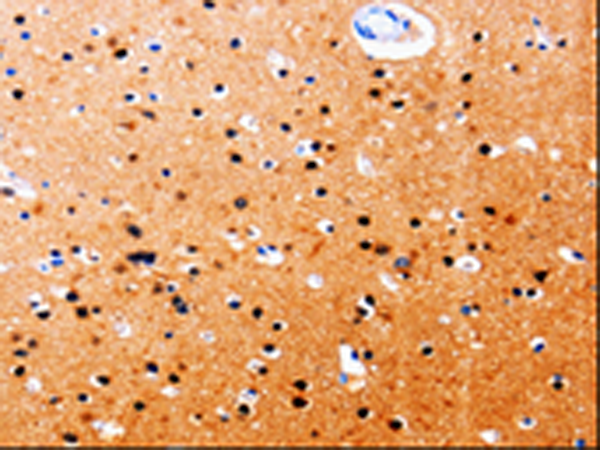

分类: 科研抗体货号: P06970别名: ADDA应用: IHC反应种属: Human, Mouse, Rat